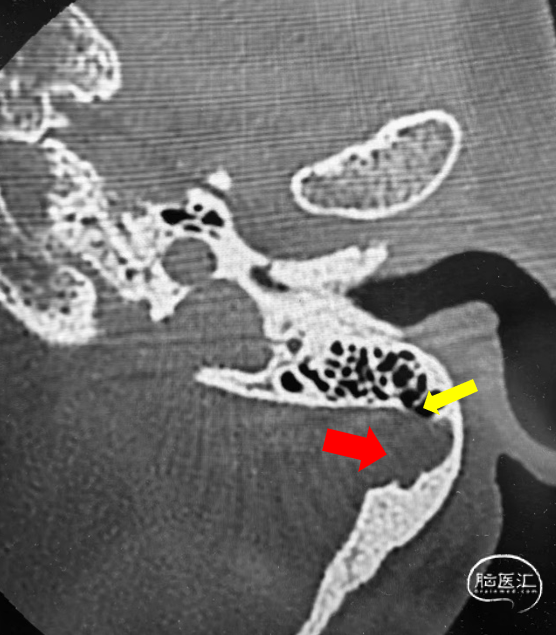

➤CT

乙状窦憩室

静脉窦狭窄

搏动性耳鸣是“血管性耳鸣”最常见的临床特征。静脉窦憩室形成或者静脉窦狭窄是主要的病因。通过门诊的CT和MR检查就能够明确诊断,初步筛选出需要外科干预治疗的患者。